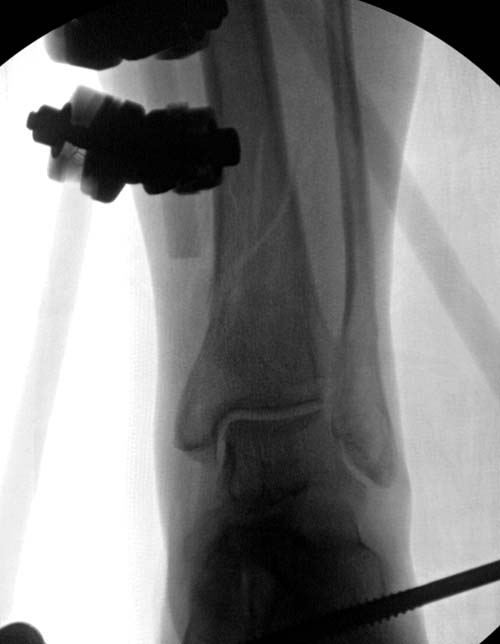

Второй случай в результате скоростной травмы, кроме пилона, вовлечение других органов! Отек при поступлении и открытый перелом на другой стороне. В таких случаях нет смысла спешить, и временный наружный фиксатор на несколько дней. После спадения отека фиксация передне-наружной пластиной. Реабилитация - ранние движения, без нагрузки.